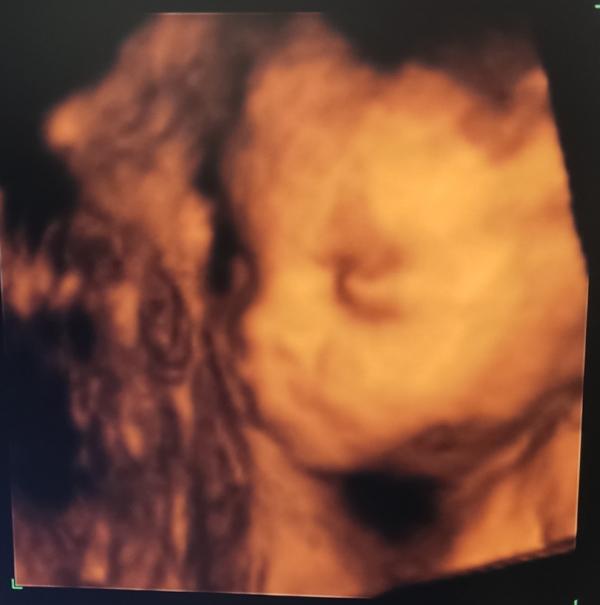

23 октября была на УЗИ, малышка подросла, весит почти 800гр, соответствует своему сроку 25 недель. Доплерометрия в норме, шейка тоже хорошая.